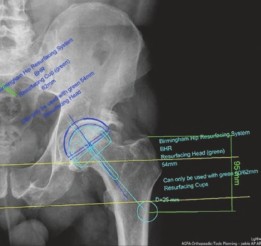

Image

Preoperative digital templating was meticulously performed. Templating for Hip Resurfacing Arthroplasty differs significantly from standard Total Hip Arthroplasty. The primary goal is to size the femoral component accurately to avoid femoral neck notching while ensuring complete coverage of the prepared femoral head. The acetabular component is then sized based on the selected femoral component, as these are paired metal-on-metal bearings. Templating indicated a femoral head size of 50 mm and an acetabular cup size of 56 mm, providing a sufficient difference to allow for optimal fluid-film lubrication and clearance.